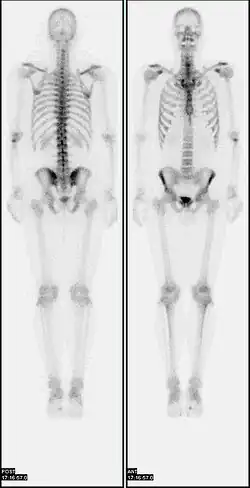

-

A nuclear medicine whole body bone scan. The nuclear medicine whole body bone scan is generally used in evaluations of various bone-related pathology, such as for bone pain, stress fracture, nonmalignant bone lesions, bone infections, or the spread of cancer to the bone. -